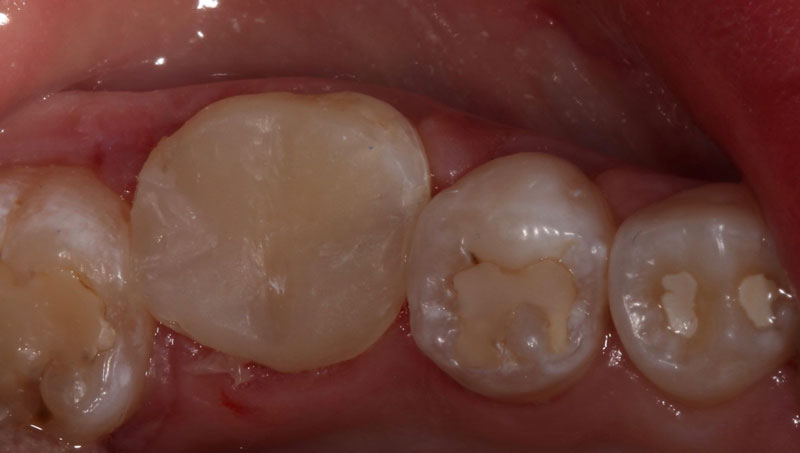

A direct pulp cap exposes a portion of the pulp tissue. This can occur due to traumatic or carious pulp exposures. In the past, when a tooth’s pulp was exposed, it almost always led to endodontic therapy. However, direct pulp capping may be feasible in specific clinical situations with modern materials that can help maintain pulp vitality, such as MTA and similar bioceramics.

Various studies have shown that direct pulp capping can be successful,2,3 and much of the research published on this topic in the endodontic community has shown that it can be a predictable procedure to maintain tooth vitality. This is even the case when a carious pulp exposure occurs in mature permanent teeth.4

In summary, the research shows that we can predictably perform pulp capping procedures using the bioceramic materials currently available.